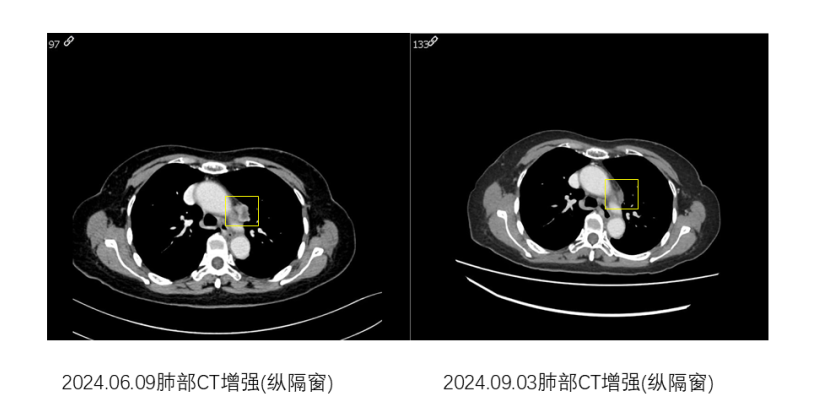

命运似乎不愿意放弃对常阿姨的考验:一年前,常阿姨的肺癌出现了缓慢进展,纵隔处淋巴结新发转移。梁淑静随后为常阿姨制定了高精度放射线疗法(IMRT,Intensity-Modulated Radiation Therapy)的治疗方案,即以高精度的放疗技术对肿瘤病灶实施精准打击。在16次放疗结束后,评估显示肿瘤显著缩小,后续采用靶向联合抗血管生成治疗维持,一直病情稳定。面对同年年底再次出现了胸廓入口处的纵隔淋巴结转移病灶较前缓慢进展,团队选择"靶向+放疗"组合拳,实现肿瘤再次退缩。

纵隔转移淋巴结治疗前后对比图